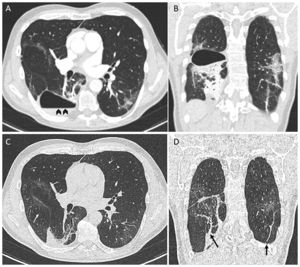

A 61-year-old man with no significant medical history presented to the emergency department with worsening dyspnea a week after close contact with someone who had COVID-19. He was unvaccinated. He was hypoxemic, and the chest radiograph showed bilateral opacities consistent with COVID-19 pneumonia and tested positive for RNA from SARS-CoV-2. Blood tests showed raised inflammatory markers. Computed tomography (CT) of the chest demonstrated bilateral ground-glass opacities. The patient was hospitalized and treated with high-flow nasal oxygen therapy, dexamethasone, and sarilumab. His clinical status improved, and he was discharged home after 1 week of hospitalization. Three weeks later, he presented again with worsening dyspnea, fever, and pleuritic chest pain. A CT pulmonary angiography ruled out pulmonary embolism (Fig. 1A, B) but demonstrated a thin-walled cystic lesion with an air–fluid level (Fig. 1A, arrowheads) that suggested an infected pneumatocele. The patient was managed conservatively with amoxicillin/clavulanic acid for 3 weeks. During the follow-up, the patient reported the disappearance of symptomatology. A subsequent CT performed 8 weeks after the diagnosis showed complete resolution of the pneumatocele (Fig. 1C, D) with persisting subpleural and parenchymal bands (Fig. 1D, arrows).